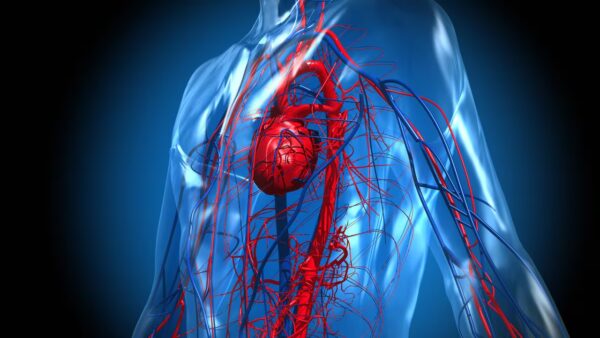

Trastornos de la circulación sanguínea

La circulación sanguínea es fundamental para mantener la salud celular y tisular debido a su papel vital en el suministro de oxígeno y nutrientes esenciales, así como en la eliminación…